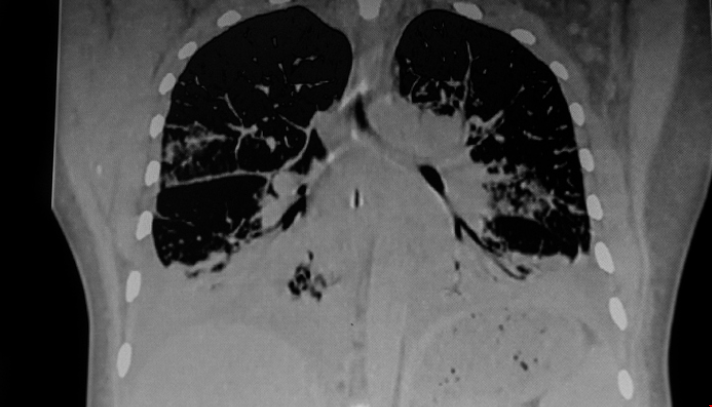

一個耗資940萬英鎊的合作研究中心,包括來自諾丁漢大學(xué)的研究人員,將加速改進測試、治療和潛在的治愈數(shù)千名患有罕見呼吸系統(tǒng)疾病(肺病疾病)的人,據(jù)悉,LifeArc罕見呼吸系統(tǒng)疾病中心將把兒童、成人和家庭與臨床專家、研究人員、投資者和行業(yè)領(lǐng)袖聯(lián)系起來。該中心的專家將進行合作,旨在克服一些阻礙罕見疾病患者獲得新的檢測和治療方法的障礙。下面就隨tops留學(xué)老師一起來看看吧!

據(jù)悉,全球有3億多人患有罕見疾病,其中每20人中就有1人與呼吸系統(tǒng)疾病有關(guān)。雖然它們本身很罕見,但它們共同造成了巨大的社會和經(jīng)濟成本。

這項合作將建立一個全英國范圍的匿名組織樣本和疾病模型庫,使研究人員能夠推進開創(chuàng)性的治療方法。它將努力降低罕見呼吸道疾病研究投資的風(fēng)險,建立罕見病患者臨床試驗所需的伙伴關(guān)系和創(chuàng)新基礎(chǔ)設(shè)施。該中心團隊還旨在提高公眾對患有罕見呼吸系統(tǒng)疾病的現(xiàn)實生活的認(rèn)識,并提高患者對可以改善其生活質(zhì)量的資源的認(rèn)識。